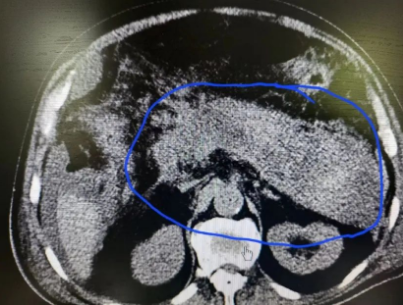

入院后,医生很快便为其安排做了腹部超声及腹部增强CT等检查,结果显示,出血坏死性胰腺炎、大量腹水……这意味着他的胰腺组织不仅出现炎症,周围的组织已被泄漏出的胰液消化腐蚀,严重到出现组织坏死、出血,产生腹水。

事不宜迟,7月18日,普外科团队在陈安良主任的组织安排下,对该病例做了全面评估,制定了详细的诊疗方案,在了解到患者胸腹部情况后,决定由何永健、刘庆顺大夫在导管机引导下对其进行腹膜后穿刺引流。当时便引流出黑褐色坏死组织液600余毫升。